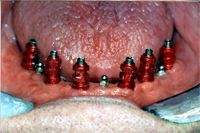

Die sechs Implantate wurden am 3. Juli unter Aufklappung im Unterkiefer gleichzeitig gesetzt. Zusätzlich habe ich zwischen die definitiven Implantate drei sogenannte temporäre Implantate gesetzt (Abb. 2, Pfeile); dies sind Implantat-Druckknopfschrauben mit einem viel kleineren Durchmesser. Diese Druckknöpfe geben der bestehenden Prothese während der Behandlungszeit einerseits bereits einen guten Halt. Anderseits können die Implantate so, unbelastet von der Prothese, perfekt im Kiefer einheilen. Der Patient ist je nach postoperativer Schwellung entweder gar nicht oder dann nur wenige Tage nach der Operation ohne Zahnersatz im Unterkiefer. Die temporären Implantate werden am Tag der Eingliederung der definitiven Arbeit oder kurz zuvor wieder entfernt.

|

Eineinhalb Monate später sind die Implantate perfekt eingeheilt. Abb. 3 zeigt das klinische Bild der eingeheilten Implantate mit entzündungsfreien Schleimhautverhältnissen. Dazwischen sieht man die drei Druckknopfimplantate als provisorische Versorgung; sie geben der Prothese guten Halt während der Behandlungszeit.